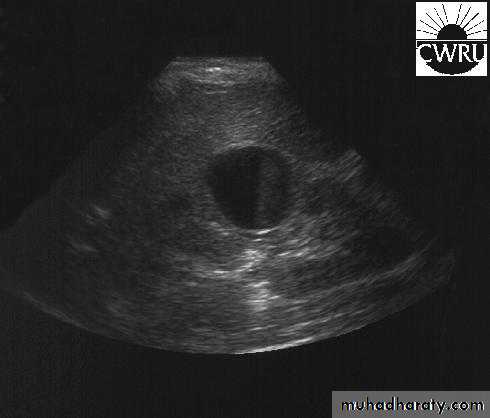

U/S: pus collection around the kidney with or without hydronephrosis.

U/S: cystic cortical lesion with internal echoes.

U/S cystic lesion with internal echoes (renal abscess)